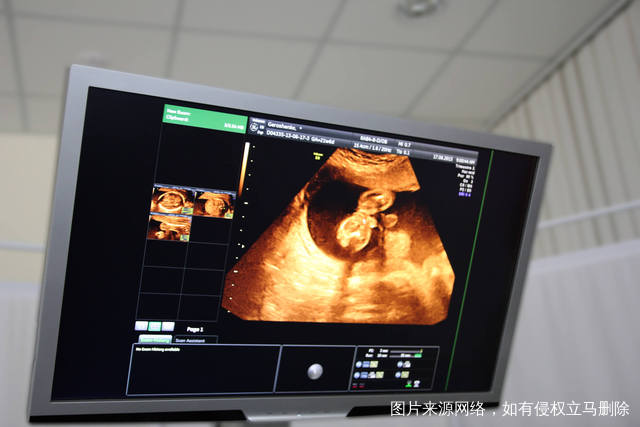

选择沈阳试管医院一定要考察一下设备先进性,精确的设备能够给每一个医生提供最精确的数据,从而把这些数据作为诊疗标准,然而很多情况下,可能大多数患者认为只要医生技术经验设备不落伍就好,但事实并非如此试管婴儿,技术对各项要求都非常高,如果没有先进设备做保障,医生很难作出判断,也会导致大多数不孕不育患者在这方面多花冤枉钱。